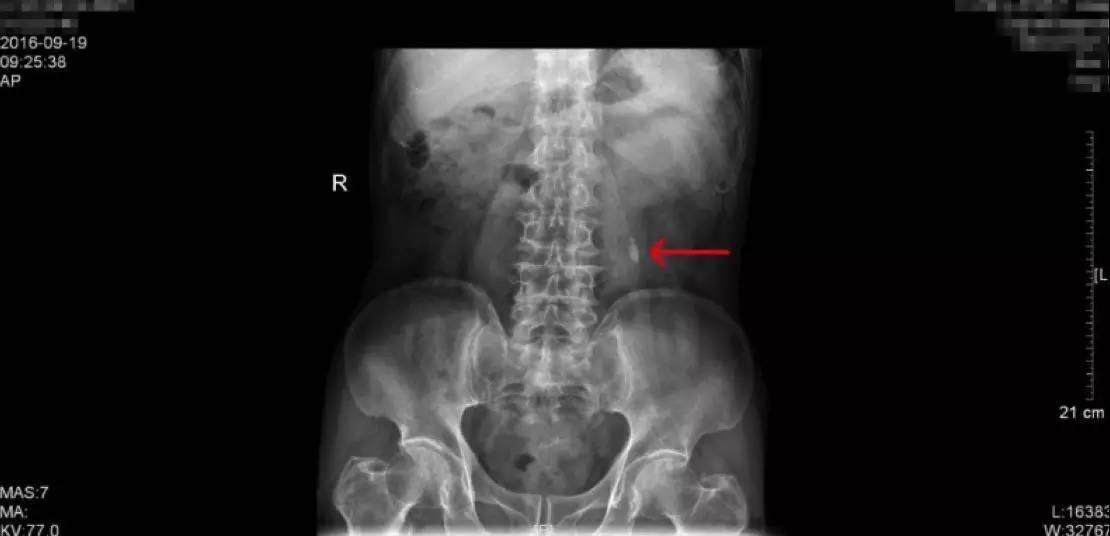

KUB检查报告:结石最大为1.2cm

KUB这一检查是泌尿系结石的常规检查之一,学名称为泌尿系平片,一般是指患者在经过肠道准备后(前一天服用泻药,让肠道内容物排出,第二天禁食,以减少肠道内容物对影像的干扰),在X线透视下摄片,涵盖整个泌尿系统,包括肾、输尿管、膀胱区域,视察这一区域有无阳性结石(酸性结石,尤其纯的酸性结石在X下无法显现,我们称为阴性结石,这一检查就无法看到,但比较少)。这一患者的KUB检查片子如上,可以看到,阳性结石表现为白色的强化,就是片子中红色箭头所指的地方,一般患者手术后也要拍一张KUB,可以和术前的检查相对比,从而直观的确认手术的效果。